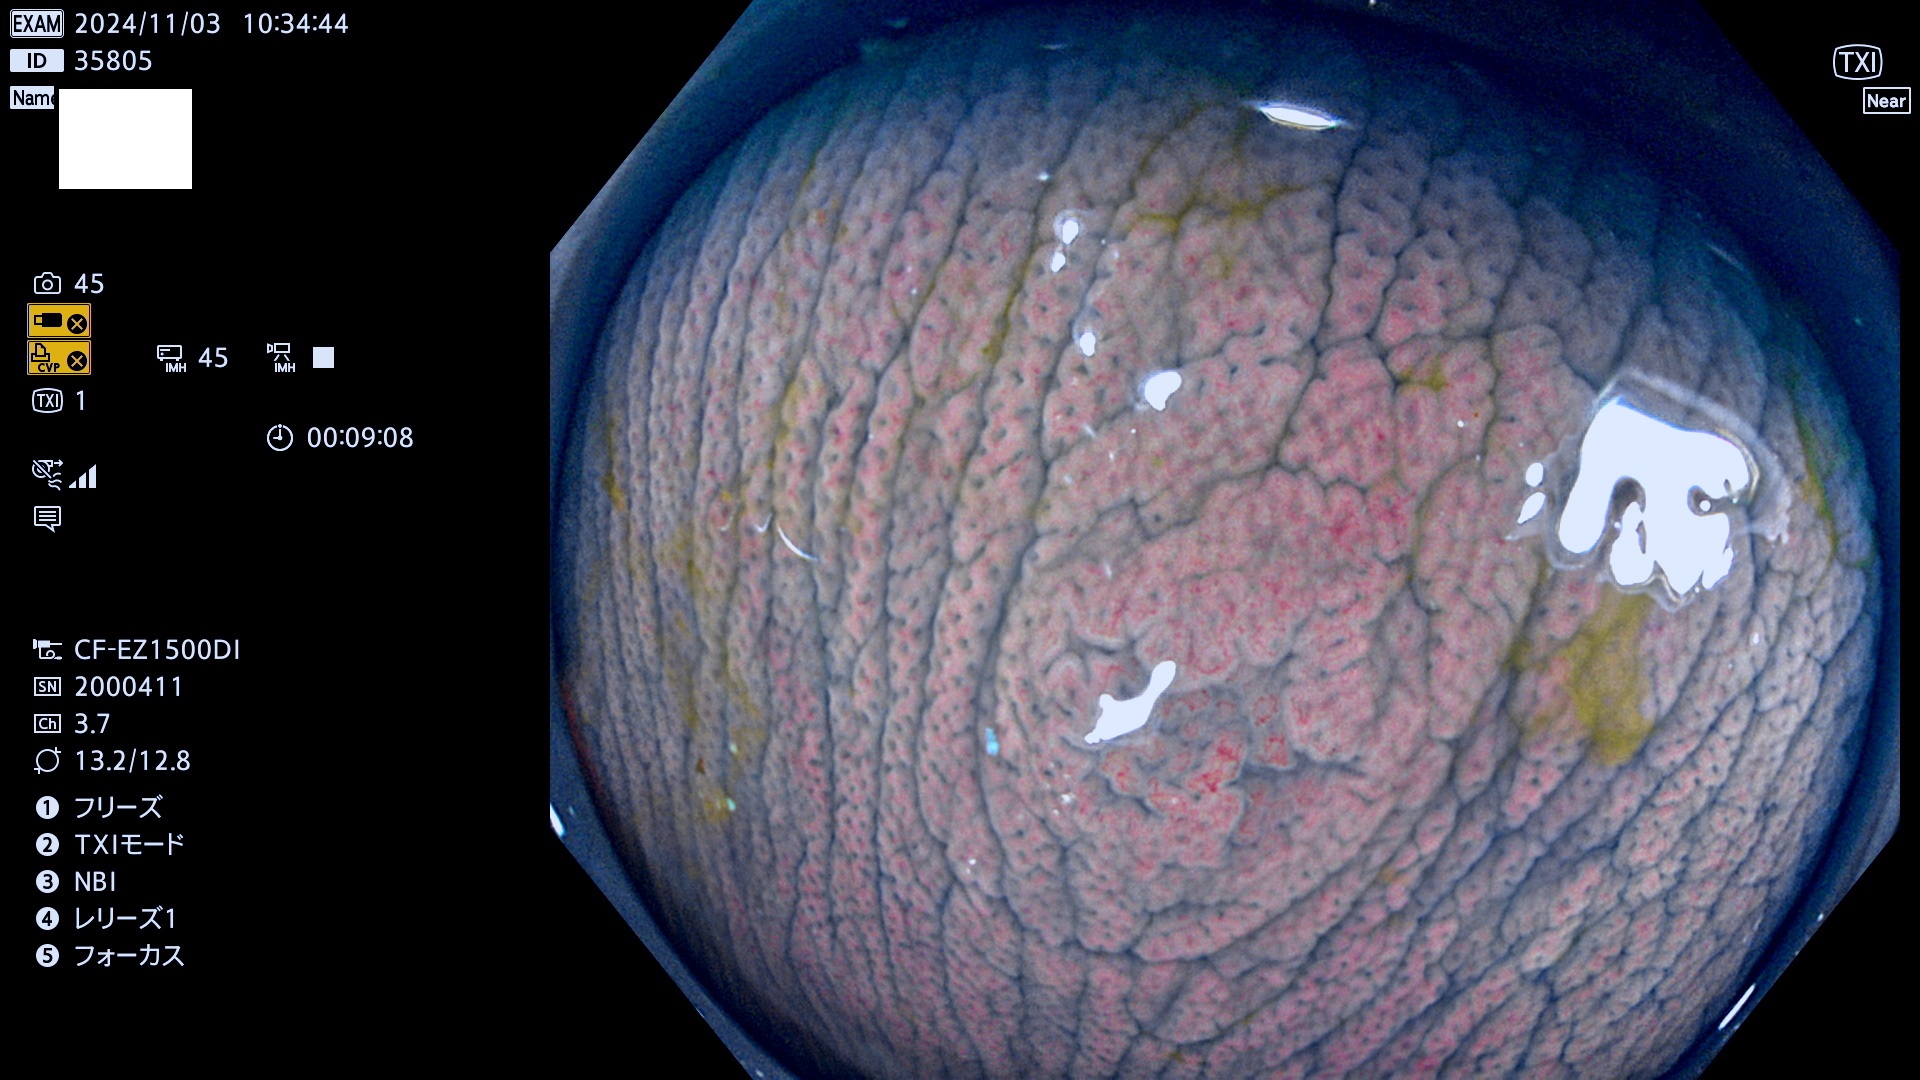

完全に平坦な物をUb、陥凹している物をUcと呼びます。最も発見が難しく危険な病変です。

毎週の検査(木・金・土・日)に発見されたUb、Uc型・腺腫を、その週の日曜の夜にUPし1週間、提示します。

抽出の対象期間 2024年10月31日〜11月3日の4日間(48件の検査)7件 (7/48=15%)